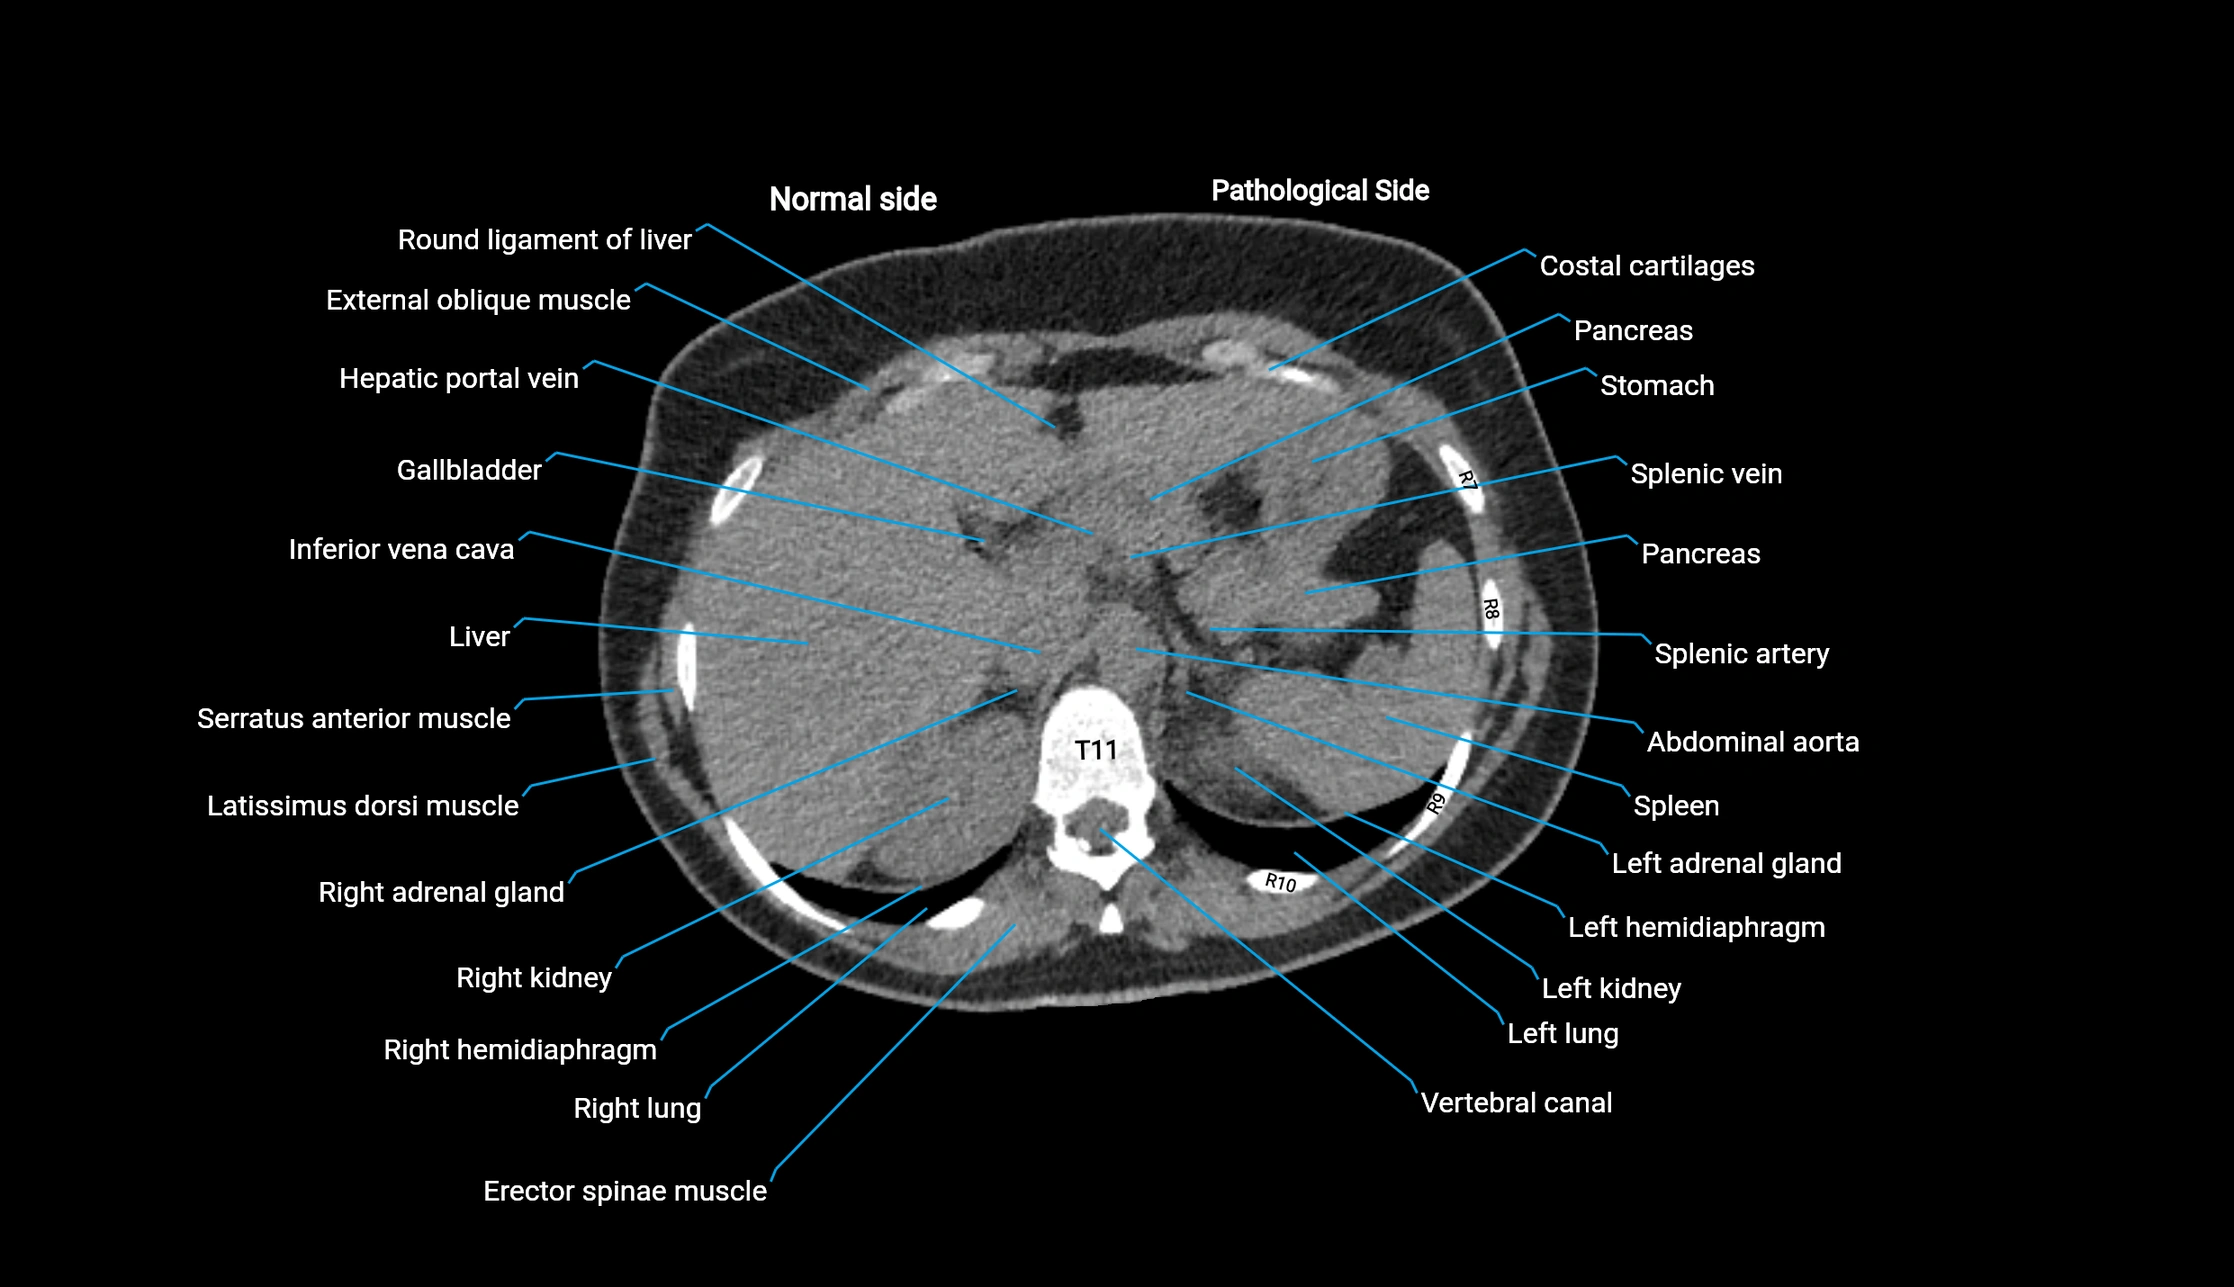

CT Appearance

Post-Contrast CT (Contrast-Enhanced CT):

• Portal venous phase:

• Anterior right portal branch enhances intensely and homogeneously

• Clearly separates from posterior branch

• Branching pattern to segments V and VIII sharply defined

• Arterial phase:

• Slight enhancement but less conspicuous than in portal phase

• Coronal and sagittal reconstructions:

• Optimal visualization of segmental bifurcation

• Used for preoperative liver mapping

• CT liver segmentation:

• RAPV acts as the principal boundary landmark for dividing anterior vs. posterior right hepatic segments